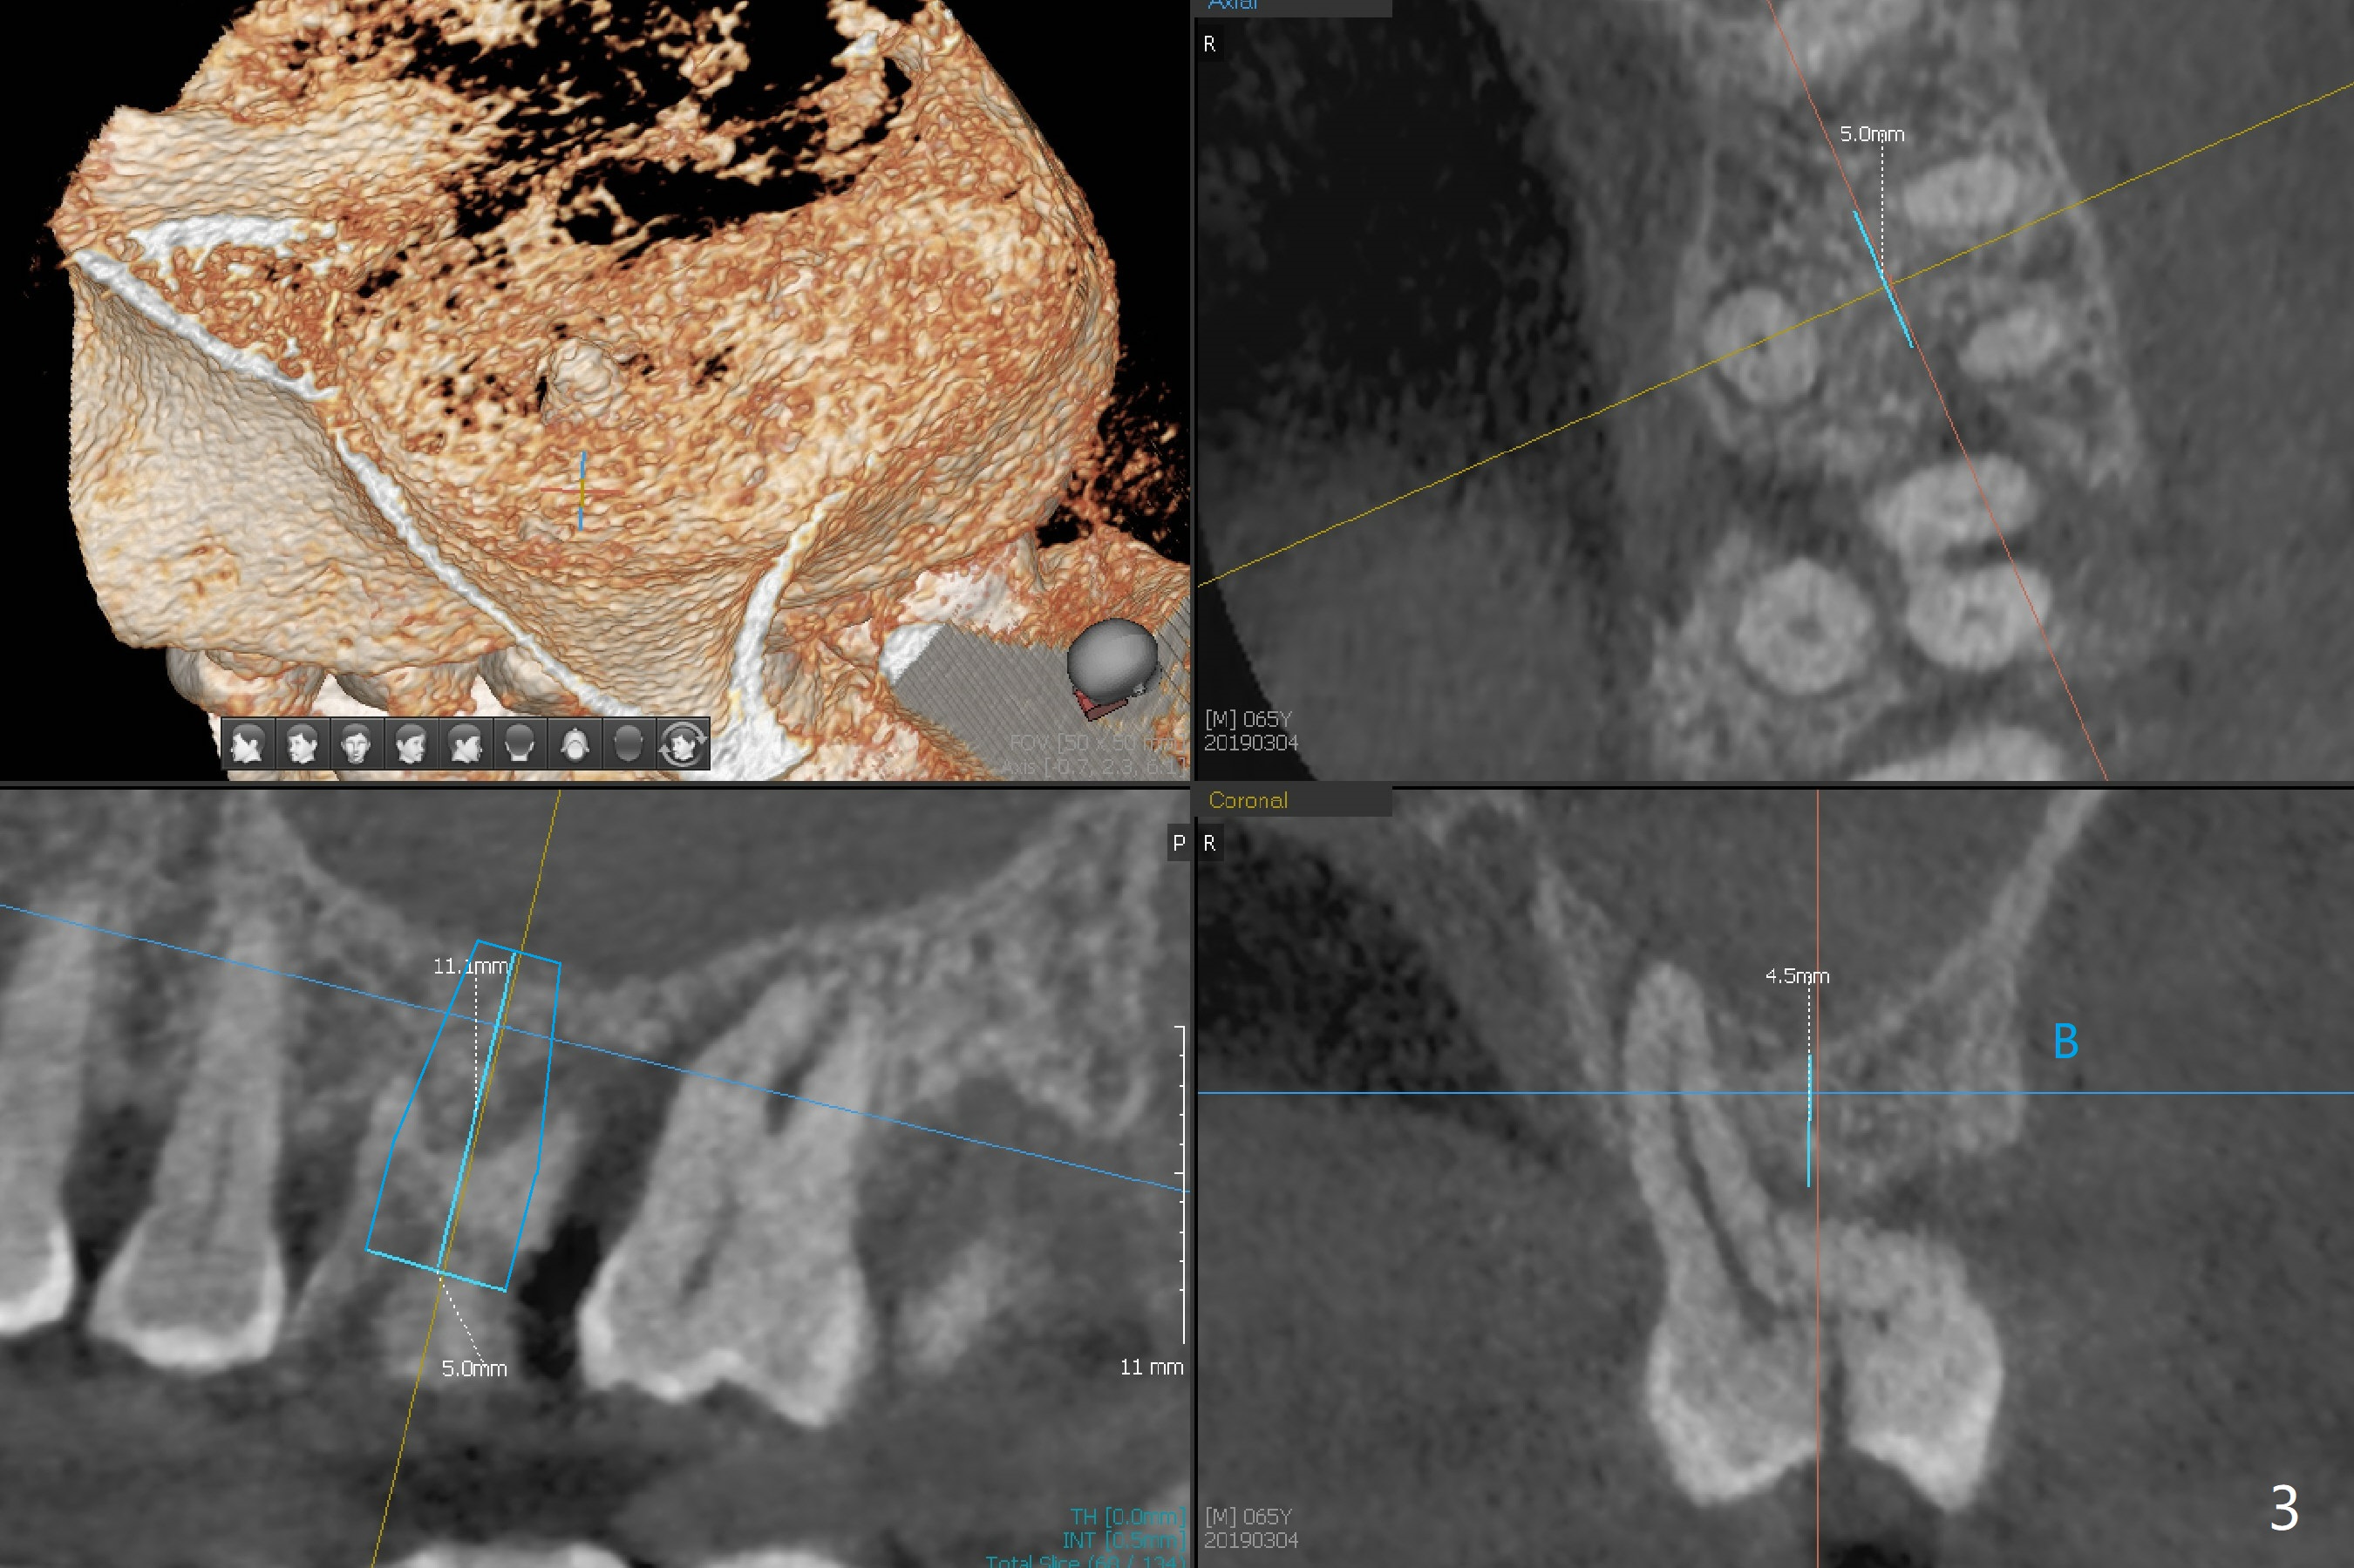

A 65-year-old man had crack tooth syndrome at #14 one month earlier (Fig.1). He shows up with crack and pain in an emergency manner (Fig.2 arrowheads). Preop CT confirms 4.5 mm bone height (Fig.3). Osteotomy will be initiated in the middle of the septum between 3 sockets (Fig.4). Depth of osteotomy is controlled with drill stoppers. After sequential osteotomy free hand, a 5x11 mm tap is used to break through the sinus floor (Fig.5) and sinus lift with Vanilla allograft. To prevent abutment screw loosening, a 5x11 mm tissue-level implant is placed; the distal thread is equicrestal (Fig.6 arrowhead). Following deeper placement of the implant (Fig.7 arrow) with a larger and longer abutment (as compared to that in Fig.6), the margin for an immediate provisional (Fig.9 white curved lines) is prepared in the coronal end of the implant (Fig.8 between arrowheads). With the tissue-level implant, the crown/implant ratio improves. Stress will be partially acting on the implant so that there is less likelihood of abutment screw loosening. The socket heals 1 month postop (Fig.10). The rough surface of the implant is exposed ~ 1 mm. With the margin modified and polished, the provisional returns to place with oral hygiene instruction. It is hoped that the gingiva will cover the exposed rough surface. The buccal rough surface remains exposed 5 months postop (Fig.11). The bone in sinus lift is mature 5 months postop (Fig.12,13). The first 1-2 implant threads are expected to be filled with mature bone in the near future (*). Since the abutment seems long enough for retention, temp bond is used for cementation (Fig.14). Water pik is being applied.